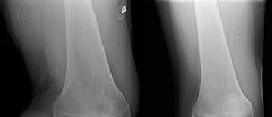

Figures 1 and 2 are the radiographs of a 35-year-old man who is brought into the emergency department after a motor vehicle collision. He is complaining of isolated knee pain. Examination reveals swelling, blood filled blisters, popliteal ecchymosis, joint line pain, and limited knee joint motion. His pulses and sensation are normal.